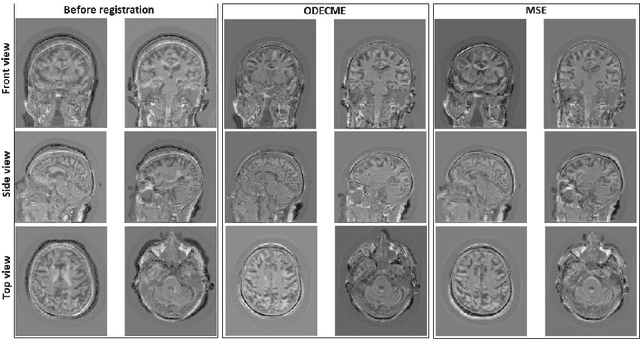

Abstract:Autograd-based software packages have recently renewed interest in image registration using homography and other geometric models by gradient descent and optimization, e.g., AirLab and DRMIME. In this work, we emphasize on using complex matrix exponential (CME) over real matrix exponential to compute transformation matrices. CME is theoretically more suitable and practically provides faster convergence as our experiments show. Further, we demonstrate that the use of an ordinary differential equation (ODE) as an optimizable dynamical system can adapt the transformation matrix more accurately to the multi-resolution Gaussian pyramid for image registration. Our experiments include four publicly available benchmark datasets, two of them 2D and the other two being 3D. Experiments demonstrate that our proposed method yields significantly better registration compared to a number of off-the-shelf, popular, state-of-the-art image registration toolboxes.